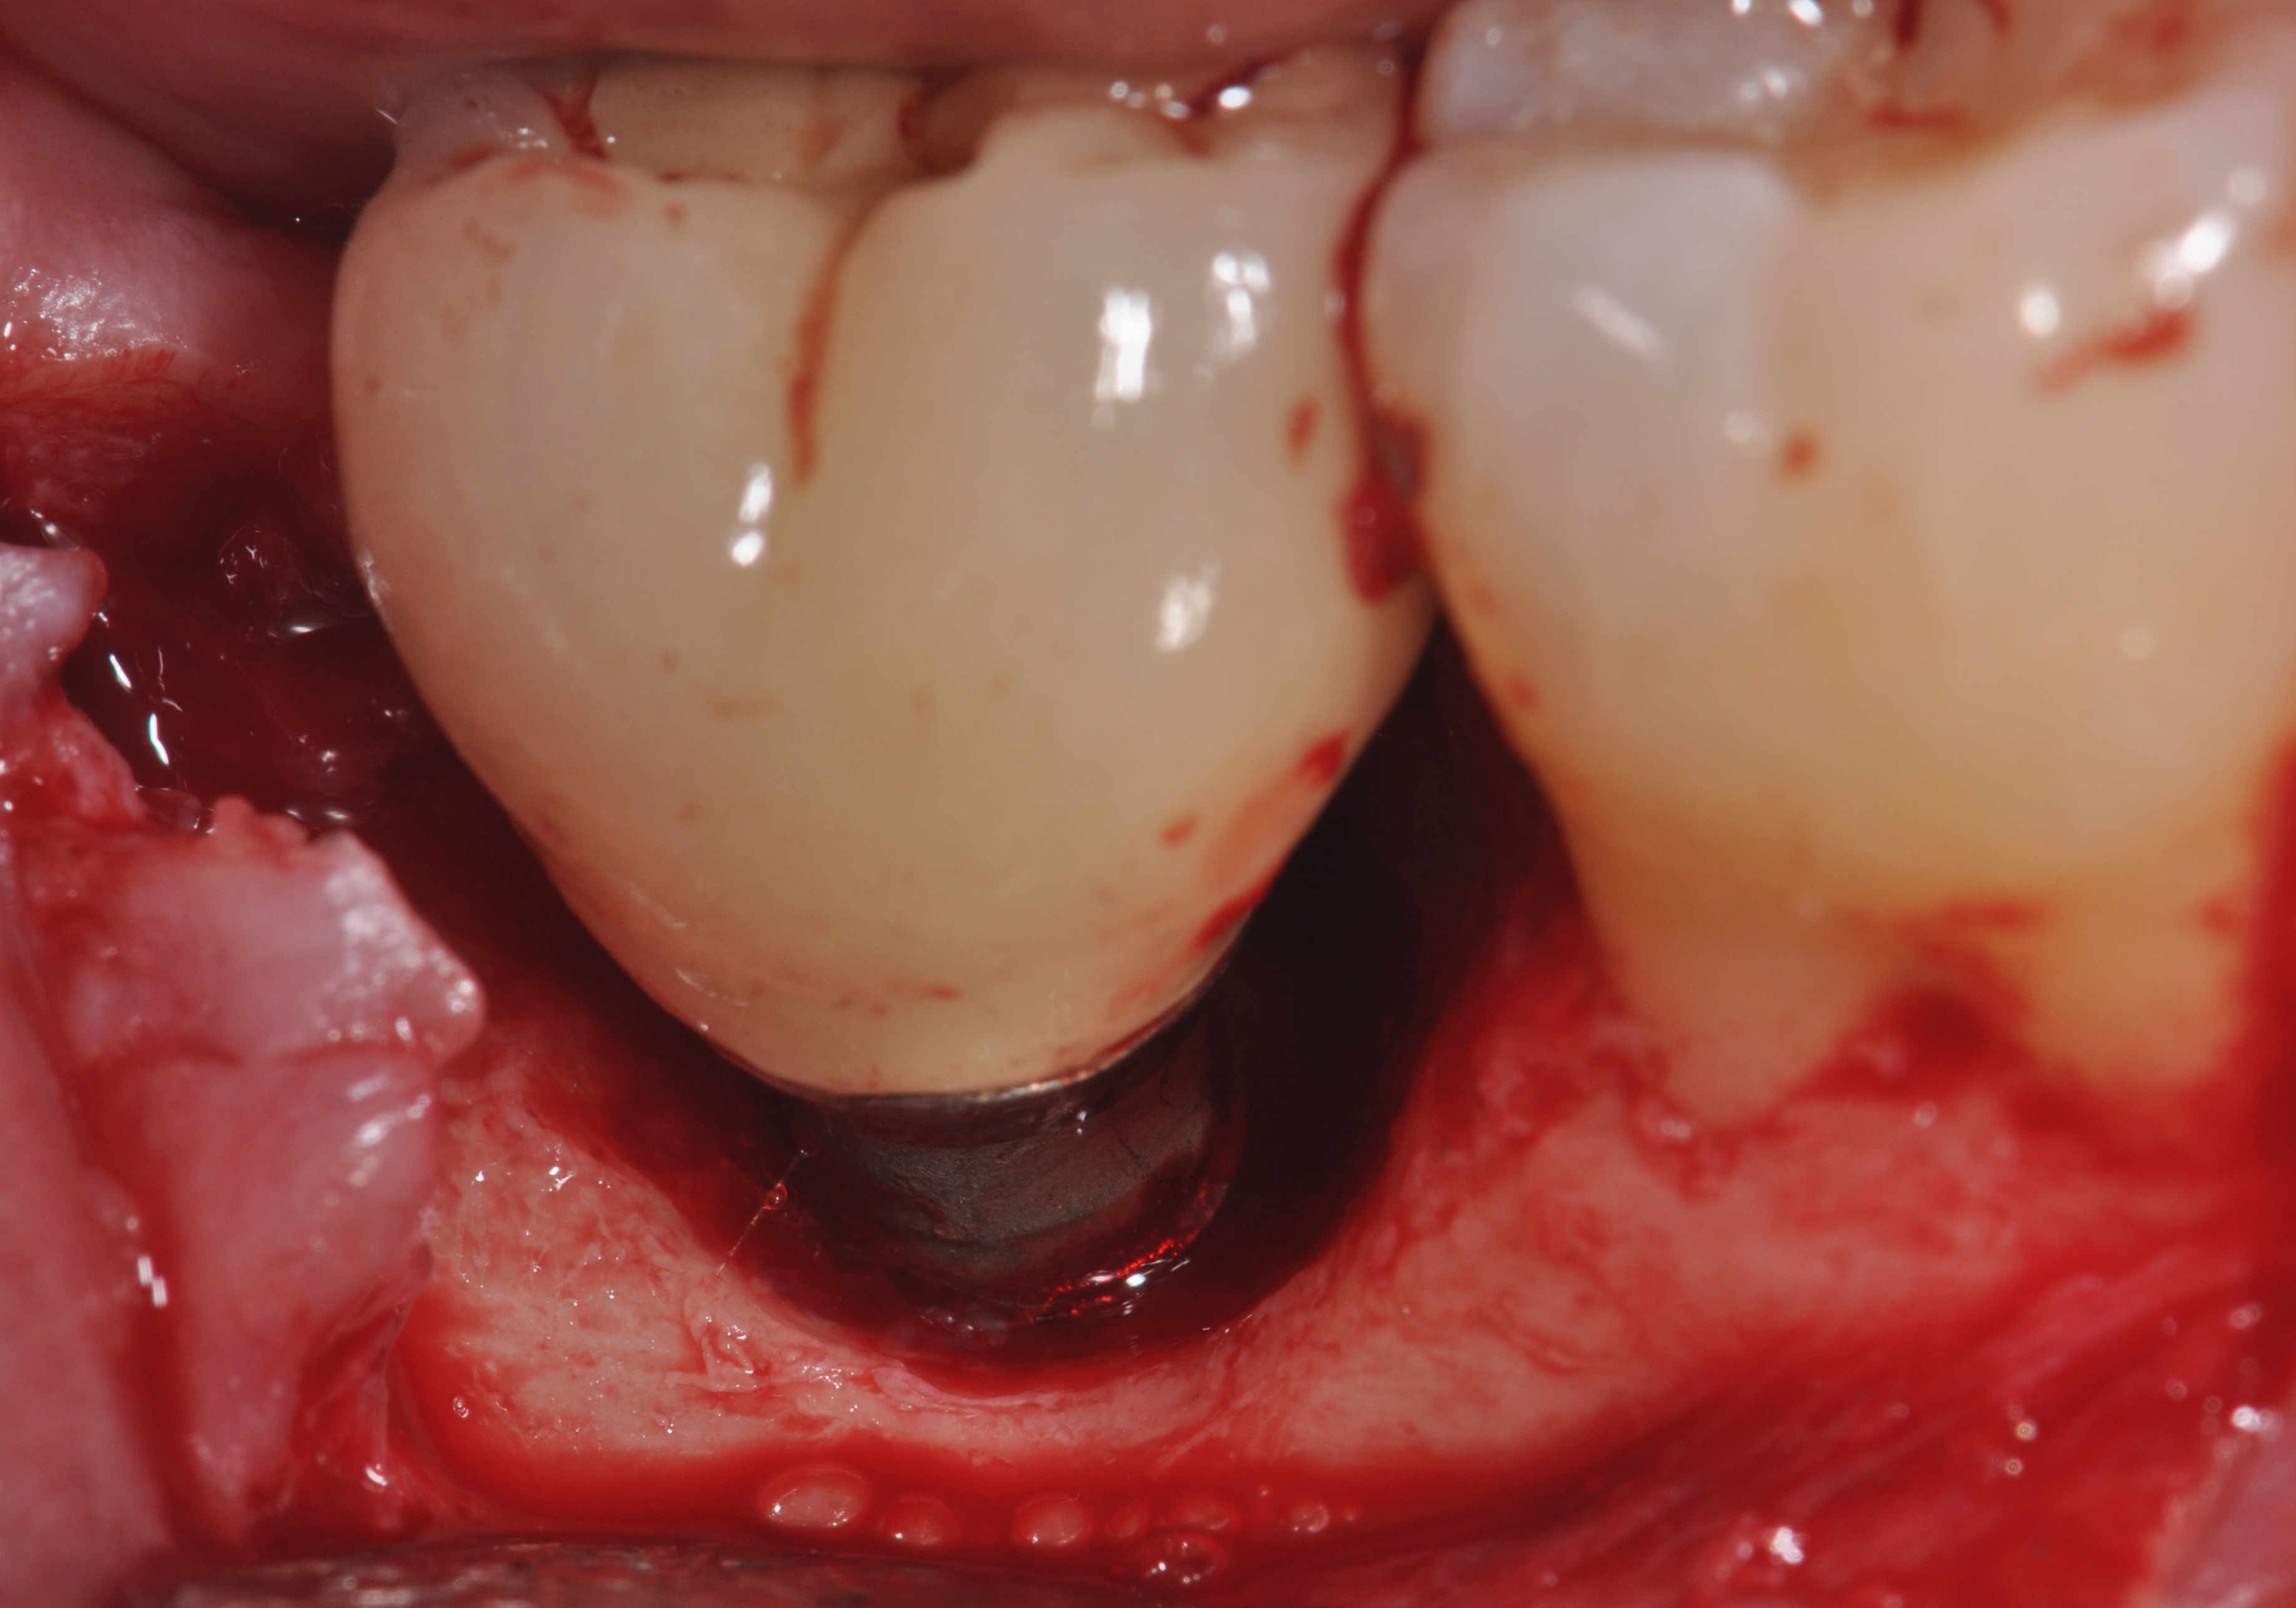

Fig 1. Clinical view of the maxillary right first premolar implant in a healthy 63-year-old woman. The swelling in the tissue surrounding the first premolar implant bled on probing and was associated with peri-implant mucositis. The lesion developed 4 years after implant placement.

Figure 1

Fig 3. Clinical view of a mandibular left first molar in an 84-year-old patient with a peri-implantitis lesion. The implant had been healthy for the previous 5.5 years.

Figure 3